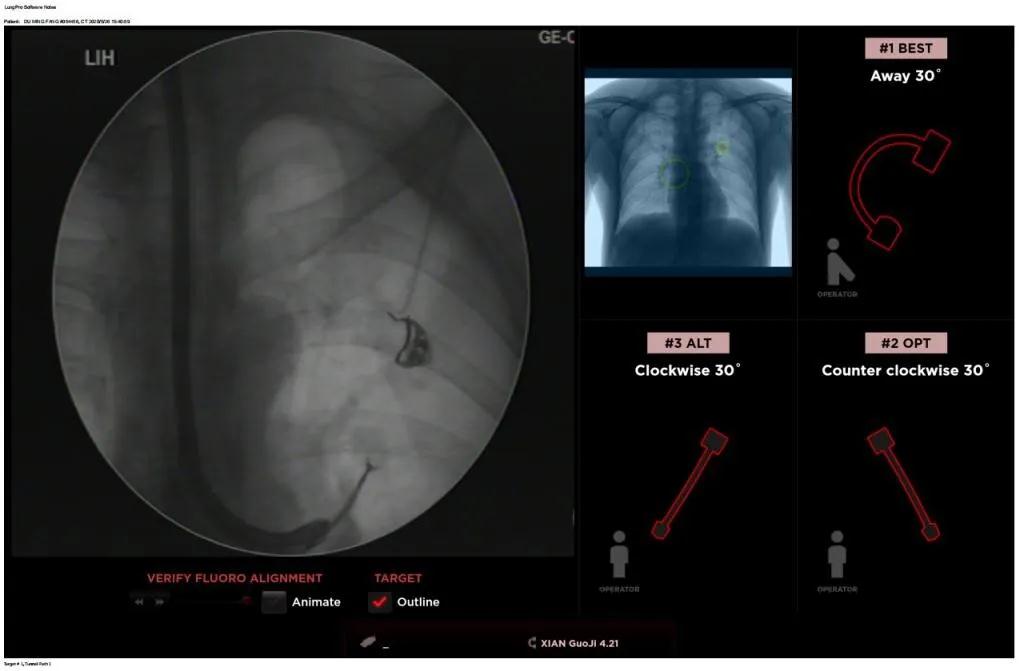

西安國際醫(yī)學中心醫(yī)院呼吸內(nèi)科完成西北地區(qū)首例LungPro全肺導航系統(tǒng)引導下BTPNA手術(shù)

近日,西安國際醫(yī)學中心醫(yī)院胸科醫(yī)院歐陽海峰副院長完成西北地區(qū)首例LungPro全肺導航系統(tǒng)引導下經(jīng)支氣管鏡跨肺實質(zhì)肺外周結(jié)節(jié)活檢術(shù)。

患者是一位59歲的男性,入院診斷左固有上葉前段肺小結(jié)節(jié),大小1.5cm*1.5cm。因為病灶與支氣管不相通,無法開展經(jīng)支氣管自然腔道的活檢,而且病變距離胸壁較遠、肋骨阻隔進針線路、病灶周圍有血管包繞,如果進行CT引導下經(jīng)皮肺穿刺活檢,則存在較大的氣胸、出血等并發(fā)癥的風險。

經(jīng)過充分的討論后,歐陽海峰副院長決定為患者實施LungPro全肺導航系統(tǒng)引導的經(jīng)支氣管跨肺實質(zhì)肺外周結(jié)節(jié)活檢術(shù)。Broncus導航系統(tǒng)LungPro具有全球領(lǐng)先獨創(chuàng)的BTPNA技術(shù)(支氣管鏡下跨結(jié)節(jié)抵達術(shù)),可以實現(xiàn)對氣道外周孤立性肺小結(jié)節(jié)的精準定位,建立直接通往氣道外病變部位的通道,以實現(xiàn)全肺的診斷及后續(xù)治療。這項技術(shù)不僅彌補了現(xiàn)有支氣管鏡技術(shù)由于受限于病變部位是否有氣道可通向以及無法準確定位病變部位而造成的較低診斷率,同時還彌補了CT引導下經(jīng)胸穿刺(TTNA)無法適用于某些特定部位如中央及肩胛骨等結(jié)節(jié)的問題,并且還避免了經(jīng)胸穿刺給患者帶來氣胸、出血的高風險,可有效提高肺部結(jié)節(jié)及早期肺癌診斷陽性率,亦可用于早期肺癌的射頻消融或微波治療,具有微創(chuàng)、安全、同期雙肺診療等優(yōu)勢。

BTPNA技術(shù)整合了虛擬導航支氣管鏡VBN、氣道內(nèi)超聲rEBUS、TBNA、高壓球囊擴張、X線輔助等多項三、四級呼吸內(nèi)鏡技術(shù)。歐陽海峰副院長有3000 TBNA、1000 rEBUS、500 VBN、800 球囊擴張方面的技術(shù)積累,10年來個人每年完成三、四級呼吸內(nèi)鏡手術(shù)1200余例,這有效保障了BTPNA技術(shù)的順利開展。

團隊術(shù)前進行了精心的準備,通過高分辨率CT建立了導航路徑,在麻醉科手術(shù)室的配合下,借助LungPro引導順利的確定了病灶部位、建立隧道并實施活檢,術(shù)后患者恢復順利出院。